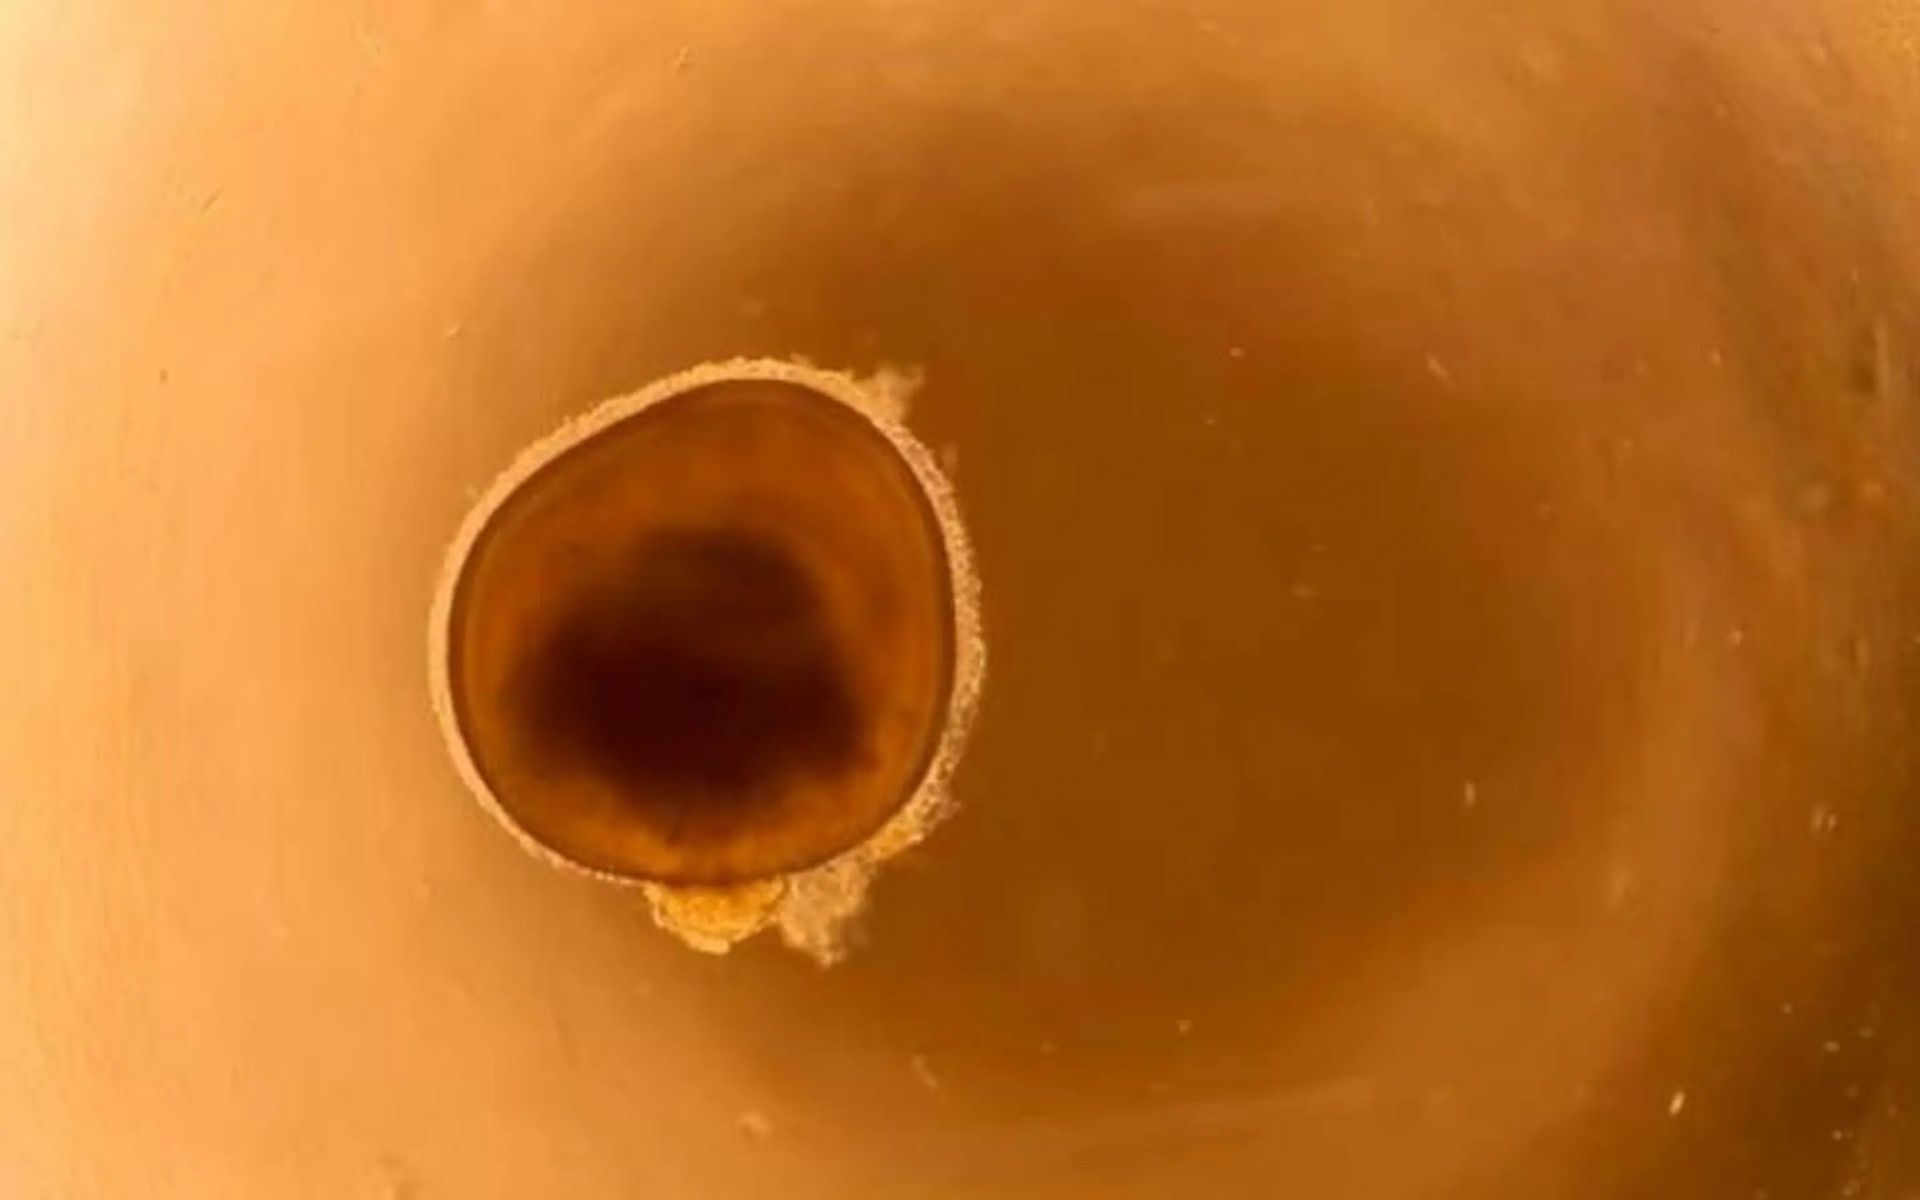

چشم کوچک پرورش‌یافته در آزمایشگاه

یکی از چشم‌های کوچک پرورش‌یافته در آزمایشگاه.